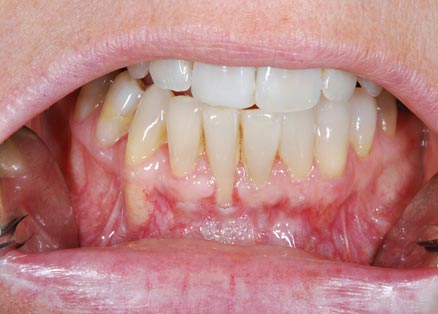

Lembo libero per correggere una recessione gengivale